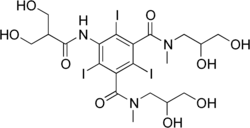

| Formula | C20H28I3N3O9 |

| Molar mass | 835.169 g·mol−1 |

Iobitridol is an iodine-containing radiocontrast agent.[2][5] The iodine atoms readily absorb X-rays, resulting in better contrast in radiography images.[9] The quality of images made with this drug is equally good as with other low– or medium–osmolarity iodinated contrast agents such as iopamidol or iohexol.[5]

After intravenous infusion, iobitridol is distributed in the circulatory system and the interstitium. The substance is only marginally bound to blood plasma proteins (to about 2%) and membrane proteins because the hydrophilic side chains of the molecule efficiently mask the central iodinated benzene ring. It is not metabolized but eliminated in the unchanged form via the kidneys by glomerular filtration without active secretion or reabsorption. The elimination half-life is 1.8 hours.[2][5]

Of the molecular mass, 45.6% is contributed by the three iodine atoms. Iobitridol is nonionic but water-soluble,[1] having some OH groups in its side chains designed to mask the central hydrophobic benzene ring.[5]

The solution has a low osmolarity of 695 (Xenetix 300) or 915 mOsm/kg H2O (Xenetix 350), which means it causes fewer allergic and allergy-like reactions, as well as less extravasation (leakage of blood vessels) than contrast agents with higher osmolarities.[2][5][10]